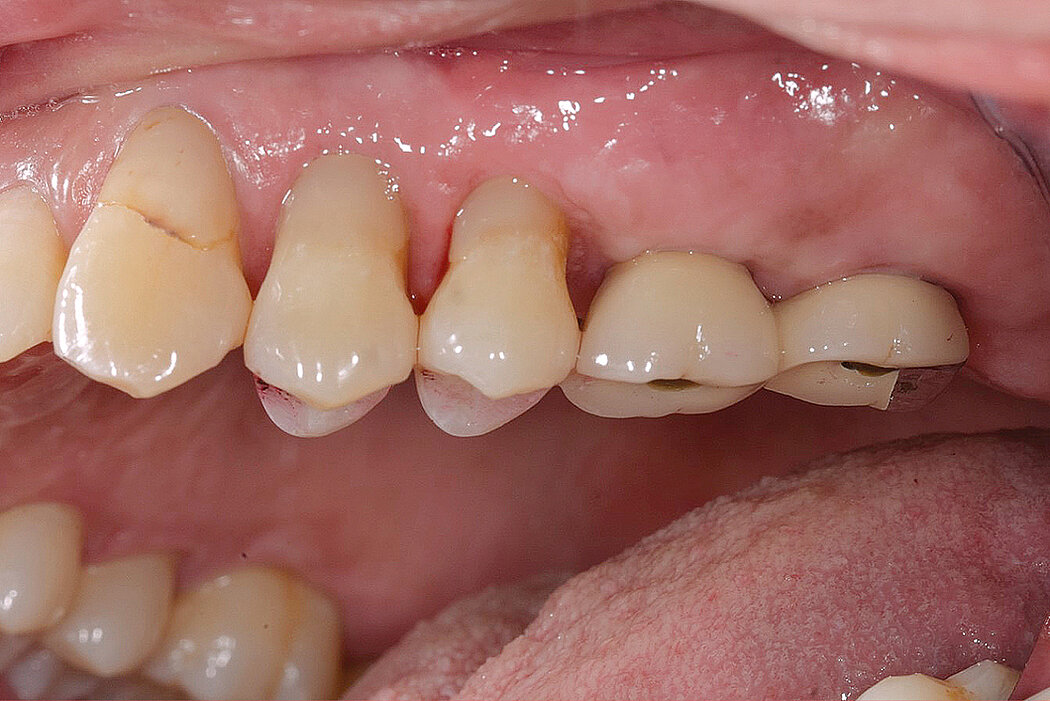

一名上颌牙保留无望的63岁女性患者,渴望进行固定修复。设计了分阶段的方案,将尖牙用作临时固位基牙,同时完成上颌窦底增量,分阶段植入种植体。该病例表现为在磨

牙部位有1-2mm的牙槽骨。在上颌窦底增量手术期间,右侧薄的上颌窦膜被大面积撕裂。使用胶原膜修复,单独使用Geistlich Bio-Oss®填充,并用Geistlich Bio-Gide®膜覆盖侧壁开窗来完成双侧窦底增量。经过较长时间的等待(经济原因)后,将种植体植入增量的上颌窦内,并采集骨样本。拔掉前牙并将临时牙冠延伸至后部种植体。随后将种植体植入尖牙部位,修复体最终制作完成。上颌窦底增量手术后随访长达13年。